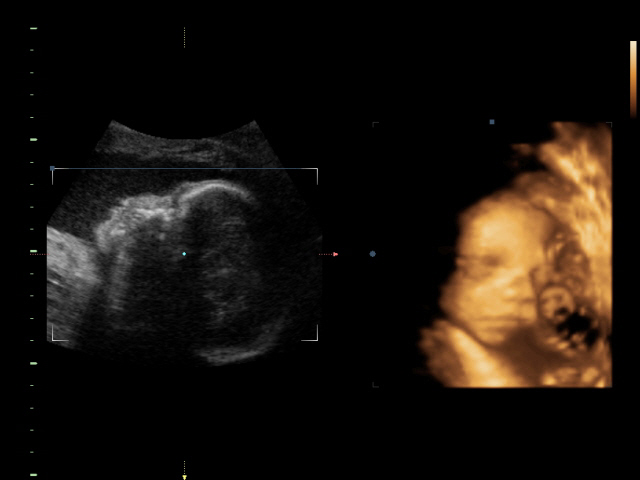

Tak prikladam dnesni foto ze 4D,no moc toho nebylo vidět:(

Malá si dávala stále před oblicej ručičky.Trvalo to cca pul hodku.